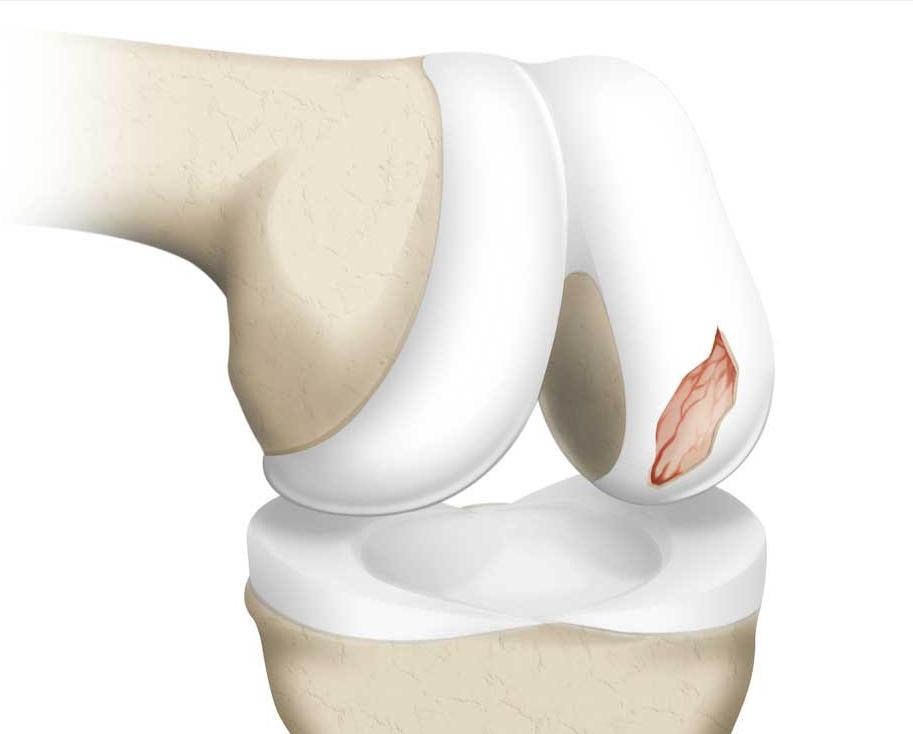

简单地解释这个桶柄状撕裂,大家可以想象成一个饼,我们把它从中间撕开两半,靠近关节腔内的这一半撕裂的半月板,就会经常在运动的过程当中造成关节的卡顿,所以小萱阿姨才会经常的出现关节的绞索。

由于已经过去了4年没有再复查核磁,谢医生给她安排了核磁检查,在复查的过程当中我们可以看到非常好的一点是,经历了4年,她的关节软骨还真就没有被破裂的的半月板明显的磨损掉,但是桶柄状的撕裂,没有任何愈合的迹象,在核磁上我们仍然可以看到非常经典的双后交叉韧带征,这说明仍然有大部分的半月板撕裂后,卡在了关节腔内。

这种关节软骨保留得非常好,没有被破裂的半月板磨损的情况,非常适合进行关节镜手术治疗,经过关节镜的手术治疗,我们可以把破裂的半月板进行部分切除,或者是尝试进行缝合,患者的疼痛将会有明显的减轻,关节功能将会得到明显的改善。